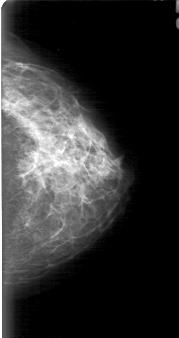

D_4030_1.LEFT_CC

LEFT_CC LINES 5056 PIXELS_PER_LINE 2671 BITS_PER_PIXEL 12 RESOLUTION 43.5 NON_OVERLAY